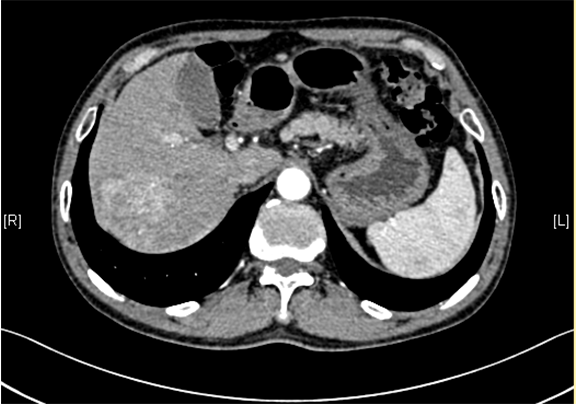

下腹部增强CT示:考虑肝右后叶肝Ca可能性大。肝顶异常强化灶,不除外不典型增生结节(DN)并癌变。肝硬化、脾大。

将0.625mm双源薄层CT资料的静脉期和动脉期Dicom格式文件导入海信CAS系统。

通过调节窗宽窗位调整CT序号,对肿瘤,肝实质,胆囊,下腔静脉,肿瘤,肝动脉、门静脉及肝静脉等进行三维重建;系统自动计算肿瘤体积和肝脏体积。

术前CT检查:

动脉期

静脉期

平衡期